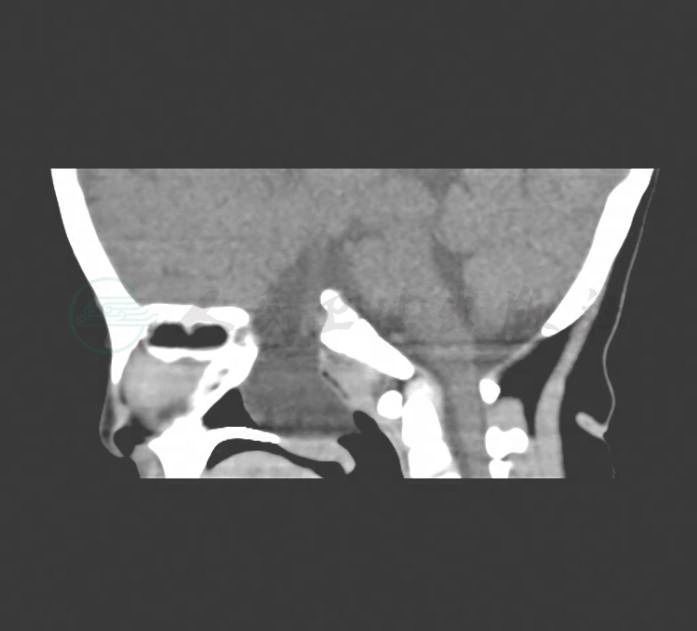

患者,女性,56岁,右侧鼻塞3年,加重1个月。伴有面部胀痛,溢泪。前鼻镜检查可见右侧鼻腔狭窄,可见来源于中鼻道暗红色新生物,呈分叶状,触之易出血,上颌窦区压痛。左侧鼻腔未见明显异常。已行入院常规检查无明显异常,鼻腔鼻窦CT检查见图1,为明确诊断,请行鼻腔活检术。

图1 患者鼻腔鼻窦CT片